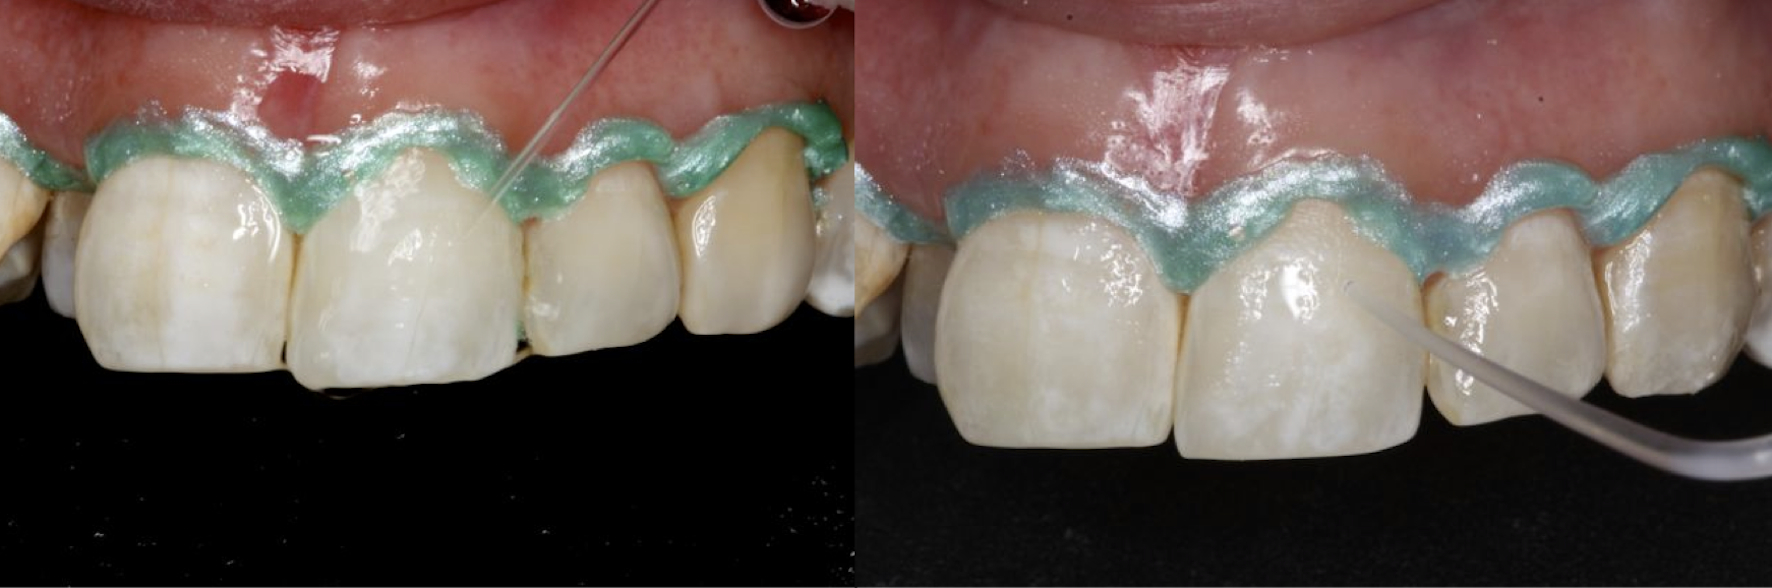

The generalized presence of stain, particularly on anterior teeth, provides an unaesthetic appearance with a negative impact on the patient. The aim of this paper is to report a case of severe chromatic alterations treated with enamel microabrasion associated with infiltration of low-viscosity resin. The intense brownish pigmentation and white spots of fluorosis lose their whitish appearance and look similar to sound enamel. This association of techniques, which might be an alternative to white-masking of intense pigmentation, showed optimal aesthetic results.